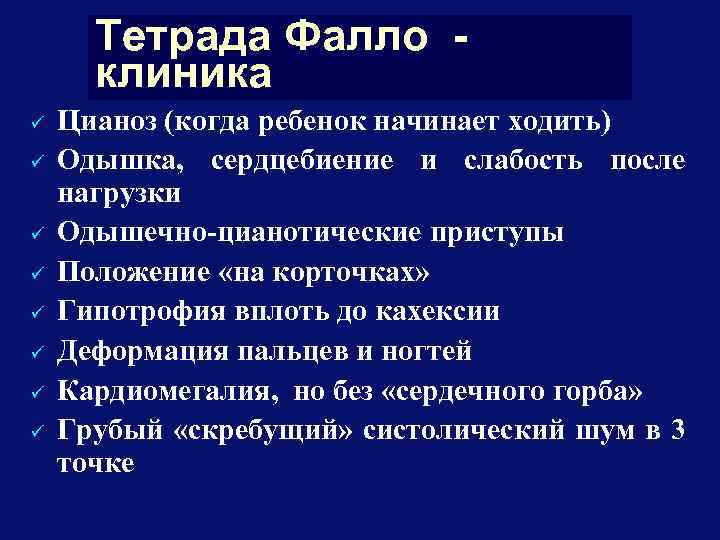

Тетрада Фалло клиника ü ü ü ü Цианоз (когда ребенок начинает ходить) Одышка, сердцебиение и слабость после нагрузки Одышечно-цианотические приступы Положение «на корточках» Гипотрофия вплоть до кахексии Деформация пальцев и ногтей Кардиомегалия, но без «сердечного горба» Грубый «скребущий» систолический шум в 3 точке